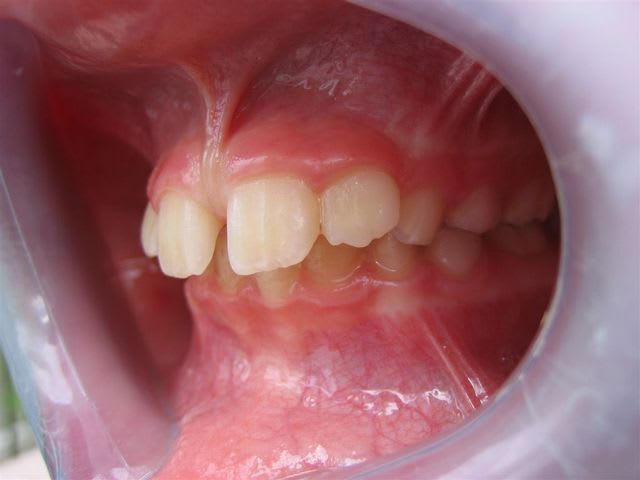

... ma gamine, bientôt 9 ans.

Père CD ... traitement d'ortho.

Mère CD ... traitement d'ortho.

Les conseils sont les bienvenus.

C’est un cas simple ou il faut juste stimuler un peu la croissance et reformer les arcades.

C’est le type même du traitement d’interception en denture mixte.

Pas de panique, petite DDM, bonne classe 2 sq,un peu de supracclusion ---> la laisser grandir un peu, et la confier à un ODF pour un peu de fonctionnelle et un alignement.

... elle est en classe I, avec une grosse supra.

TT "fonctionnel" prévu dans qqs semaines.

... c'est en cours ... un appareil de chez Rocky Mountain va être mis en place, à porter environ 16 heures/jour; il va falloir que je m'en fasse expliquer le principe lors de la séance de pose.